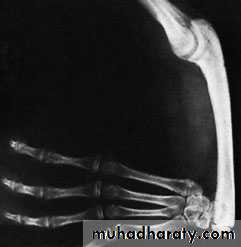

Very rarely an intercalary segment in the upper limb fails to developthe forearm or hand may be attached directly to the trunk,

or the hand is attached to the humerus.

also known as phocomelia